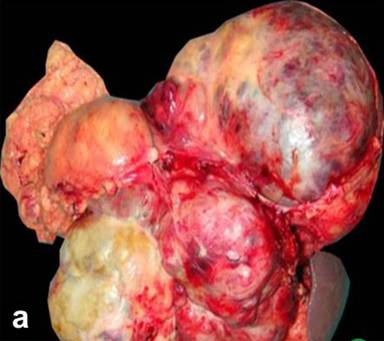

Gross and Microscopic Pathology (Table 3, Figure 2ab, Figure 3a-d)

On gross evaluation, the tumors ranged from 2.4 cm to 35 cm with mean size of 14 cm. Twelve (63.2%) of 19 were larger than 10 cm (hence high risk category) [56] of which 8 occurred in females. Gross morphology was described in 17 cases. Majority (12, 70.6%) were purely or predominantly solid with focal cystic components, 3 (17.6%) were predominantly cystic with peripheral solid areas, and 2 (11.8%) were entirely cystic, whereas areas of hemorrhage and/or necrosis were additionally present in 4 out of 19 cases (21.1%). In only two cases (10.5%), presence of peripheral compressed pancreatic tissue was described. Rest it was not. The lesions simulated solid pseudopapillary neoplasm in one (5.2%), malignant cystic epithelial neoplasm in 3 (15.8%; 2 serous, 1 mucinous), and ductal adenocarcinoma in rest (15/19, 78.9%).

Figure 2. Gross specimen showing a large lobulated tumor in relation to the body and tail of the pancreas (a.) which showed cystic and hemorrhagic degeneration with blood clot on cut section (b.). Compressed pancreatic tissue was also evident towards the periphery of the tumor. |